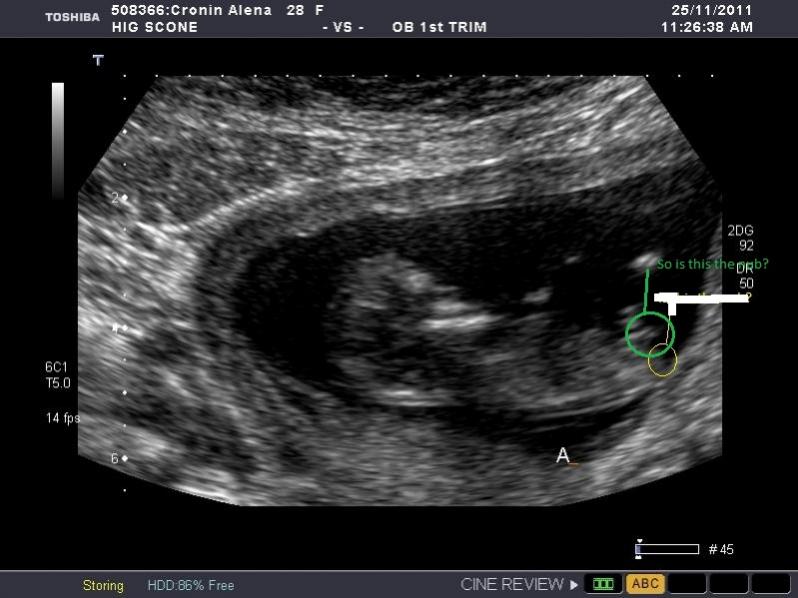

NEW PHOTO POSTED FURTHER DOWN to see if I have it correct this time

Still obsessing here. In my other post most people said boy but say its to early to really tell at 11.3 weeks. Bub is measuring 12.1 weeks thought. Some people also say that they can only see the nub in one of the many photos I posted. I am going to repost the pic I THINK might be the one I can see the nub in. But to me it looks girly not boy and most people guessed boy in this site other site eveyone guessed girl.

So is this the nub and if so does it look like a boy or girl nub?